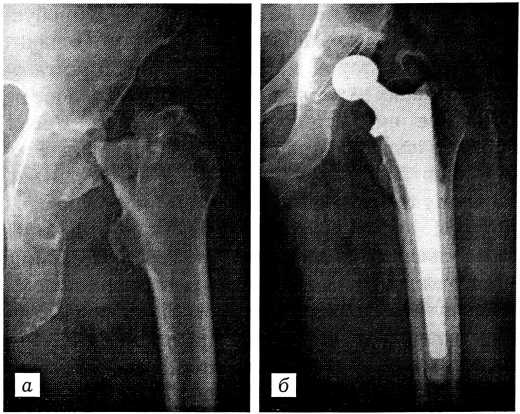

Чаще мы использовали полиэтиленовые чашки нашей конструкции — с антилюксационным козырьком и бортиком по периметру для уплотнения костного цемента (чашки ИСКО-РУДН) или имеющие в дополнение к этому четыре выступа на куполе и смещенное книзу гнездо для головки (выпускаются фирмой «Имплант МТ») (рис. 2).

Рис. 2. Рентгенограммы тазобедренного сустава больного с посттравматическим коксартрозом. а — до операции; б — через 1 год после эндопротезирования эндопротезом СФЕН (фирма «Имплант МТ»).